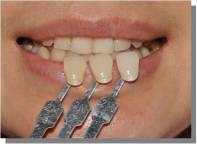

干货集结:

快门 1/125 、 光圈 F25 、 ISO 100

拍摄主体面向光源,不可多反光

比色板与牙齿保持于同一水平线